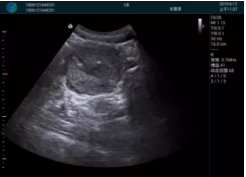

M20查看:囊內回聲均勻,邊界清晰,囊壁光滑

M20引導抽吸術后囊腫消失,原區(qū)域空腔形成,脂肪層與腺體層架構發(fā)生改變